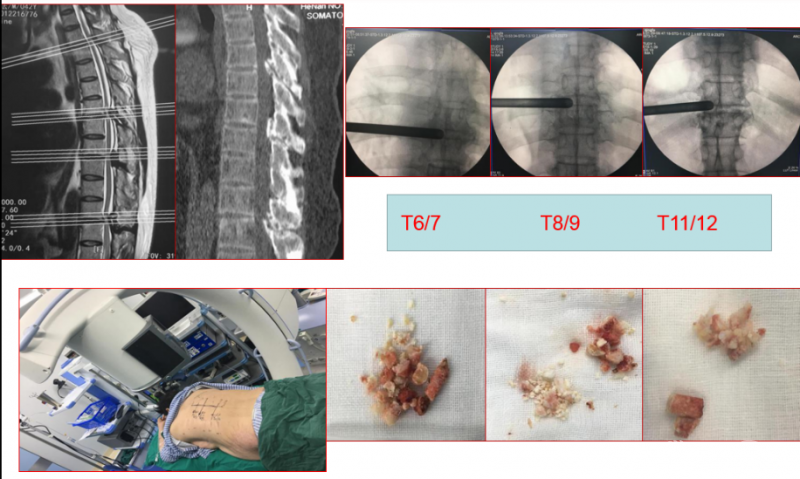

Case1:胸椎黄韧带钙化可视化的治疗

手术资料

择期分次手术资料